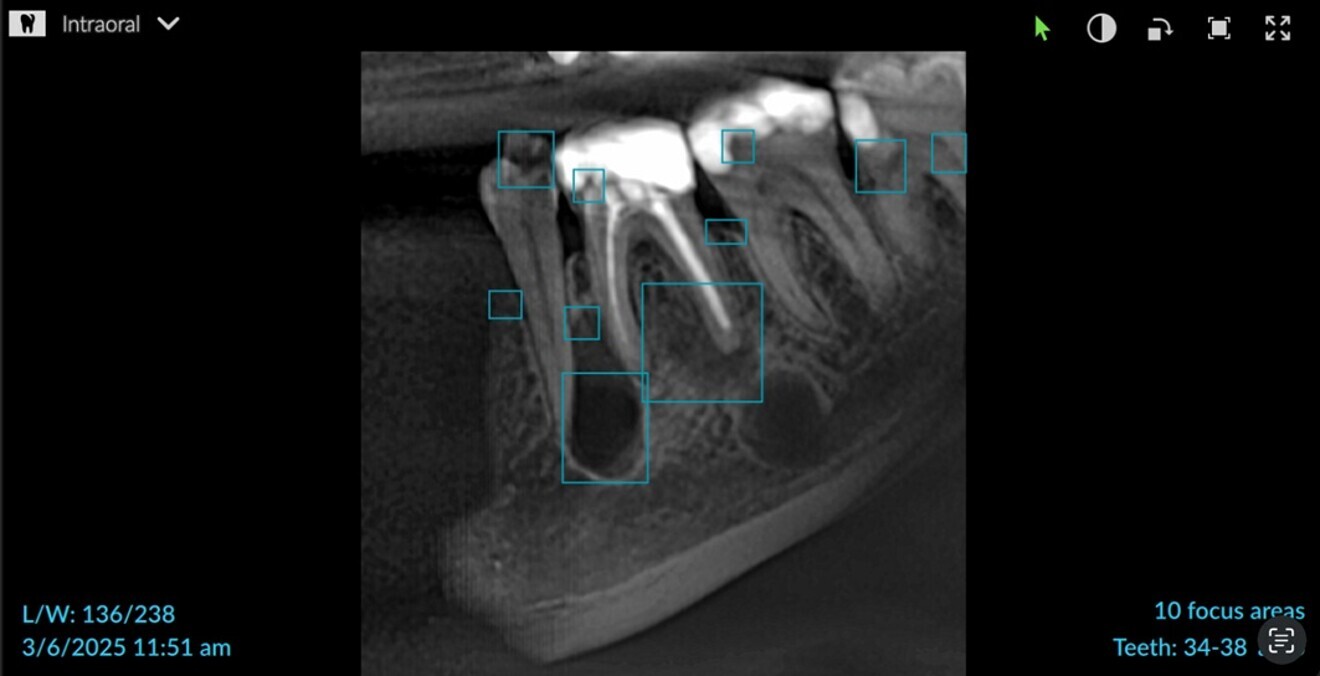

The scan was then analysed using DTX Studio Clinic (DEXIS; Fig. 2). It fully supports importing and viewing of any DICOM file and can be used for 2D radiographs and intra-oral photographs. The platform integrates multiple artificial intelligence tools in 2D and 3D workflows, boasting several innovative features. One of its most useful features is that the software processes the image in order to produce the best quality to support the clinician in accurate diagnosis.

Fig. 2: Application of artificial intelligence to the 2D radiograph to focus on multiple areas in DTX Studio Clinic.